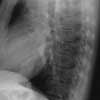

Figure 2

A chest radiograph and sputum evaluation for acid-fast bacteria (AFB) are ordered.

The chest radiographs show alveolar infiltrate in the right upper lobe, with no hilar adenopathy. The cardiac configuration is normal. The sputum shows AFB. These findings in a person with RA who has been treated with infliximab and who has a 3-week history of respiratory symptoms strongly suggest pulmonary tuberculosis, D.